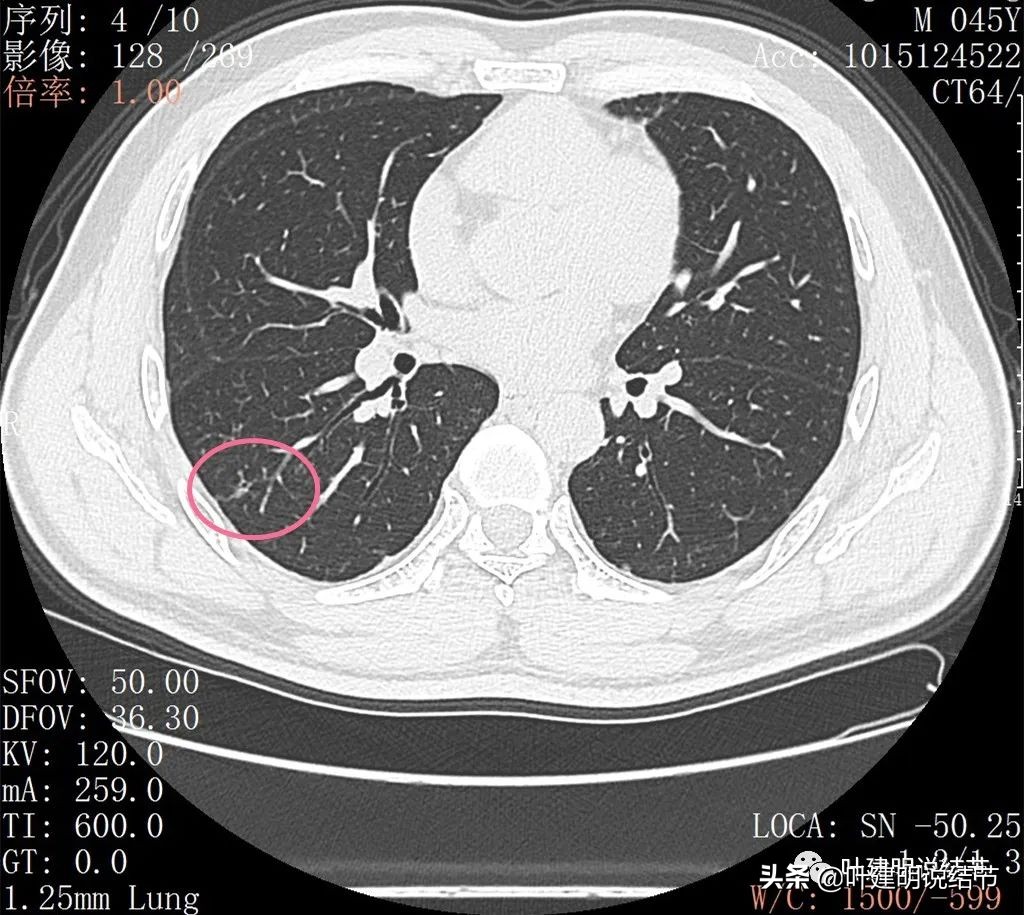

丽水的某A,今年45岁,男性。几个月前检查发现右肺下叶磨玻璃病灶,在当地医院检出后,某市医院胸外科专家看过后考虑恶性可能性大,建议其手术。但他听朋友介绍于2022年2月份来我门诊就诊,予以查了胸部CT平扫加右下叶靶扫描。我们先来看他当时的影像:

2022年2月平扫:

右下叶淡而散在的磨玻璃影

整体轮廓有点清楚,似见血管走行于病灶处

密度略不均